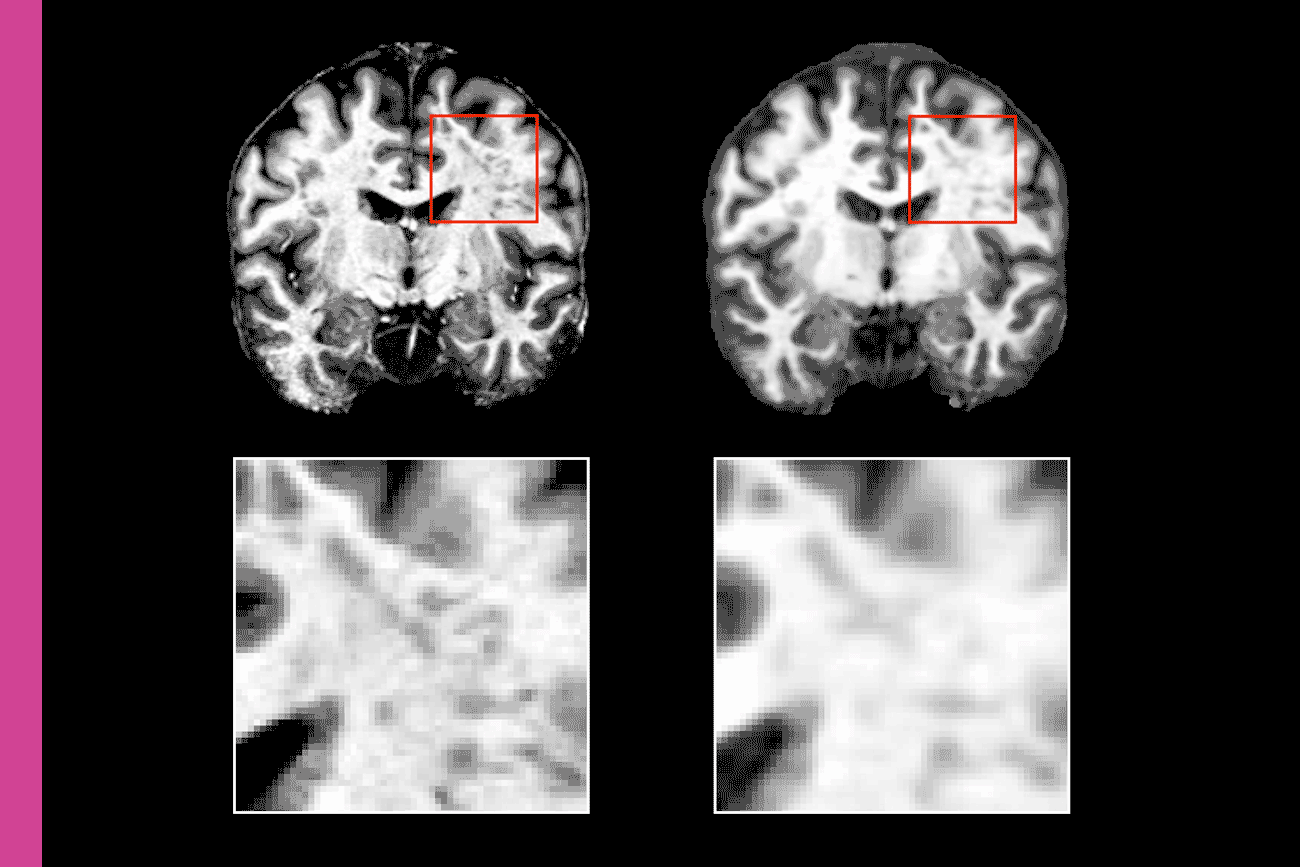

Magnetic Resonance Imaging (MRI) is particularly useful for studying the soft tissues that make up our livers, hearts and brains. Unlike X-rays, MRIs can produce finely detailed images of these organs and, in the case of the brain, help physicians detect tumors, subtle signs of strokes and changes over time.

Most MRIs in the U.S. are performed with lower resolution 1.5T (Tesla) or 3T MRI systems that may miss signs and symptoms of conditions like multiple sclerosis and traumatic brain injury. Stronger 7T machines, which produce higher resolution images, could help, but their high cost is why only about 110 were in use globally as of 2022.

UCSF assistant professor of Neurology Reza Abbasi-Asl, Ph.D., led a team that used a form of AI to enhance the resolution of standard MRIs featuring traumatic brain injuries. The technique dramatically improved 3T MRI images, putting them roughly on par with 7T images, while outperforming other types of AI-enhanced MRIs.

Abbasi-Asl and team constructed small, anonymous databases of pairs of traumatic brain injury MRIs. Each pair contained MRIs of the same injury: one low-resolution, 3T version, and another high-resolution, 7T version. The team created machine learning models that connect bits of information based on data patterns to boost low-resolution images before comparing them to their high-resolution partners.

The outcomes of these models identified patterns and features that were hard to detect for the human eye in 3T MRIs, using them to understand how to improve image quality — boosting specific details while minimizing “noise” like grainy specks.

“Our findings highlight the promise of AI and machine learning to improve the quality of medical images captured by less advanced imaging systems,” Abbasi-Asl said.